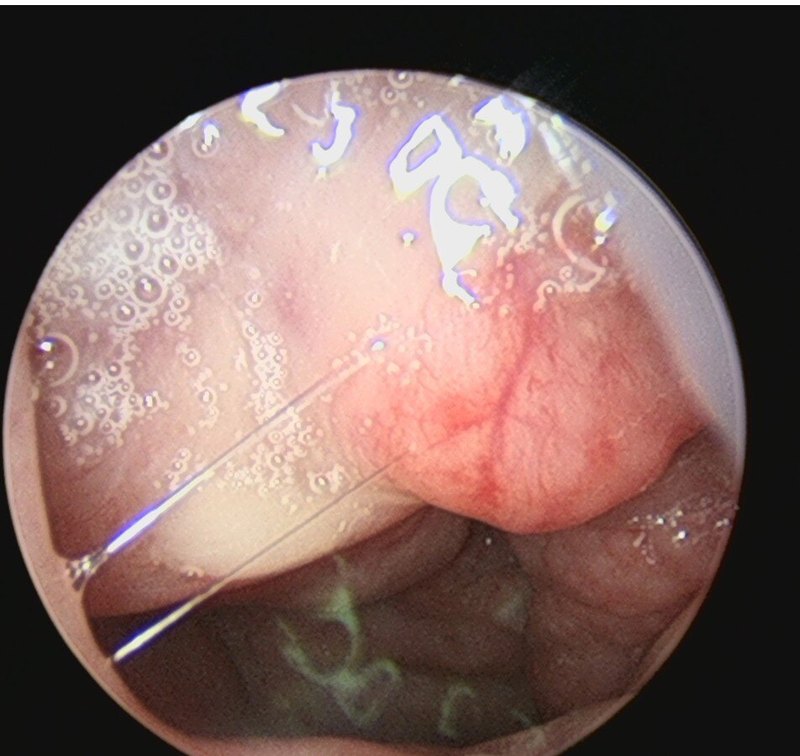

來自廣東佛山20歲的潘先生,1月前無明顯誘因出現(xiàn)右側(cè)鼻腔出血,量不多,訴無明顯鼻塞流涕,無鼻癢、打噴嚏,無頭痛頭暈,無惡心嘔吐。對癥治療后好轉(zhuǎn),但較反復(fù)。剛開始沒有太重視,覺得是天氣熱,吹空調(diào)多,干燥導(dǎo)致的。但是老是反復(fù)發(fā)作,就有點擔(dān)心,怕有問題。最后還是決定找耳鼻喉鄭立崗醫(yī)生看看,做了鼻內(nèi)鏡檢查后發(fā)現(xiàn)潘先生的鼻腔中有一個紅色的腫物,出血的原因非常有可能就是這個腫物導(dǎo)致的。耳鼻喉鄭立崗醫(yī)生建議患者手術(shù)切除腫物,所以就入院了。安排了全麻鼻內(nèi)鏡下鼻腔腫物切除手術(shù)和鼻咽部活檢手術(shù)。插管全麻后就開始了手術(shù),在鼻內(nèi)鏡下順利切除了鼻腔的腫物。術(shù)中出血不算多,由于鼻咽部腫脹,這次順便也做了鼻咽部的活檢,來排查鼻咽癌的可能。整個手術(shù)用時約30分鐘,非常的順利。術(shù)后查房患者無明顯的不適,無手術(shù)相關(guān)的并發(fā)癥。最后組織學(xué)檢查出來了,鼻腔的腫物是血管瘤,切除就沒有問題了。鼻咽部是炎癥,沒有多大問題,多點鍛煉身體,睡早點就可以了。